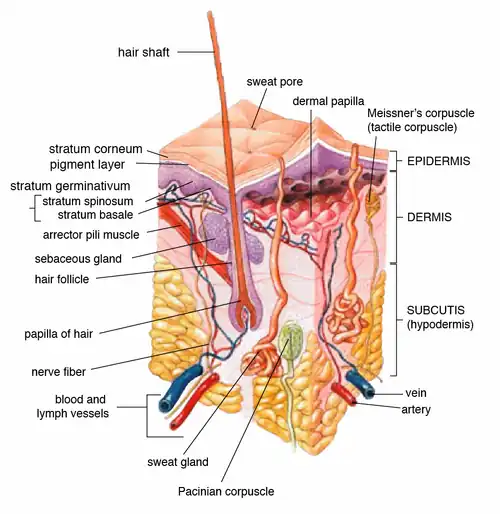

Epidermis

The epidermis is composed of the outermost layers of cells in the skin which together with the dermis forms the cutis. The epidermis is a stratified squamous epithelium, composed of proliferating basal and differentiated suprabasal keratinocytes which acts as the body's major barrier against an inhospitable environment, by preventing pathogens from entering, making the skin a natural barrier to infection. It also regulates the amount of moisture released from the body by diaphoresis (sweating).

The epidermis has no nerves or vessels. It is nourished by diffusion from the dermis. The epidermis constists of

- keratinocytes (95% majority)

- melanocytes

- Langerhans cells

- Merkel cells

Rete ridges (wrinkles) are epidermal thickenings that extend downward between dermal papillae. These are or interest to nurses where they can be mapped as "Langer's lines" indicating the direction in which they usually lie. "Crow's feet" at the outer edge of the eyes is an example of skin wrinkles which typically allow movement in one direction. Incisions along these lines will leave the least obvious scar, while incisions across these lines will cause dog-eared puckering of the healed skin.

Blood capillaries are found beneath the epidermis, and are linked to an arteriole and a venule.

Dermis

The dermis is the largest layer of skin between the epidermis and the hypodermis which is responsible for giving the skin its structural support. The dermis consists of white fibrous tissues containing elastic fibers to allow the skin to stretch. It also contains blood vessels, lymph vessels, hair follicles and glands that produce sweat. This helps regulate the body temperature and keeps the skin from drying out. [Tabbners Nursing Care, 5th Edition, Chapter 37, Page 617]

Hypodermis

The hypodermis is the innermost and thickest layer of the skin, it is specialised in accumulating and storing fats, known as adipocytes it also acts as an energy reserve.

Its purpose is to attach the skin to underlying bone and muscle as well as supplying it with blood vessels and nerves also its Fat serves as padding and insulation for the body.

The hypodermis also fastens the skin to the underlying surface, provides thermal insulation, and absorbs shocks from impacts to the skin.

Nerves

Glands

Sweat glands include the apocrine gland which may act as a sex attractant also opens in to the hair follicle. Eccerine gland which control body temperture.